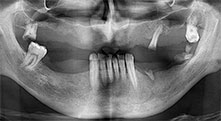

Bratu: We routinely use the instruments for harvesting bone blocks and splitting alveolar ridges. We also use the Piezomed B6/B7 for osteotomy of impacted teeth and removing failed implants. All indications that require deep, clean cuts.

Could you describe briefly, for example, your procedure for mobilizing bone blocks for transplantation?

Bratu: We prefer to harvest bone from the external oblique ridge of the posterior mandible, not from the interforaminal region. After the soft-tissue incision, we use the new saws to define the amount of bone to harvest. With this approach, we also use them for the entire preparation in almost 80% of cases. We may also use other piezo instruments and then at the end a chisel to mobilize the block. We find that this is a very effective surgical technique.

Bratu: We like to use the sandwich technique for augmentation in the lateral mandible. A bone cover is prepared with the piezo saw and the crestal fragment is fixed with microscrews. We place a mixture of autologous bone and xenogenic bone replacement material in between. This works very reliably. You should always ensure sufficiently dimensioned vertical cuts when splitting the alveolar ridge in the mandible. Otherwise the bone may fracture easily.

Bratu: I consider piezo surgery a great leap forward in oral surgery. The technique makes bone preparation safer and easier. Little bone is lost, for example in extractions. This is very important in the aesthetic zone, particularly if immediate implantation is planned. Piezo surgery is also safer for soft tissue: injuries to membranes in the sinus are basically history, as are nerve injuries when bone blocks are being harvested. Data indicating reduced postoperative swelling and pain are also available. Piezo surgery is also ideal for preparation of sinus septa. And last but not least, our patients benefit from the atraumatic nature of this technology.